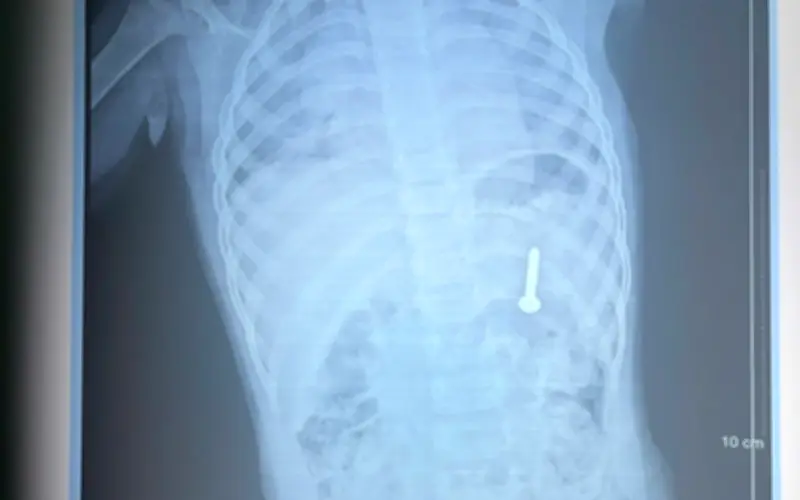

Sau khi thăm khám và chụp X-quang, các bác sĩ xác định dị vật nằm trong dạ dày của bệnh nhi. Nếu không được can thiệp ngay, dị vật có thể gây ra các biến chứng nghiêm trọng như thủng đường tiêu hóa, xuất huyết, và nhiều nguy cơ khác đe dọa tính mạng.